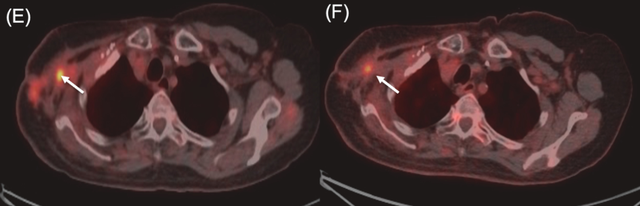

病例3

一名76岁女性,患有三阴性浸润性导管癌。其后出现胸壁和腋窝复发,侵犯臂丛神经并导致右臂完全瘫痪。BNCT治疗后右肩部和皮下病灶消退,仅残留小腋窝结节,2025年11月的随访胸部CT显示,患者照射部位保持部分缓解,局部控制得到改善。